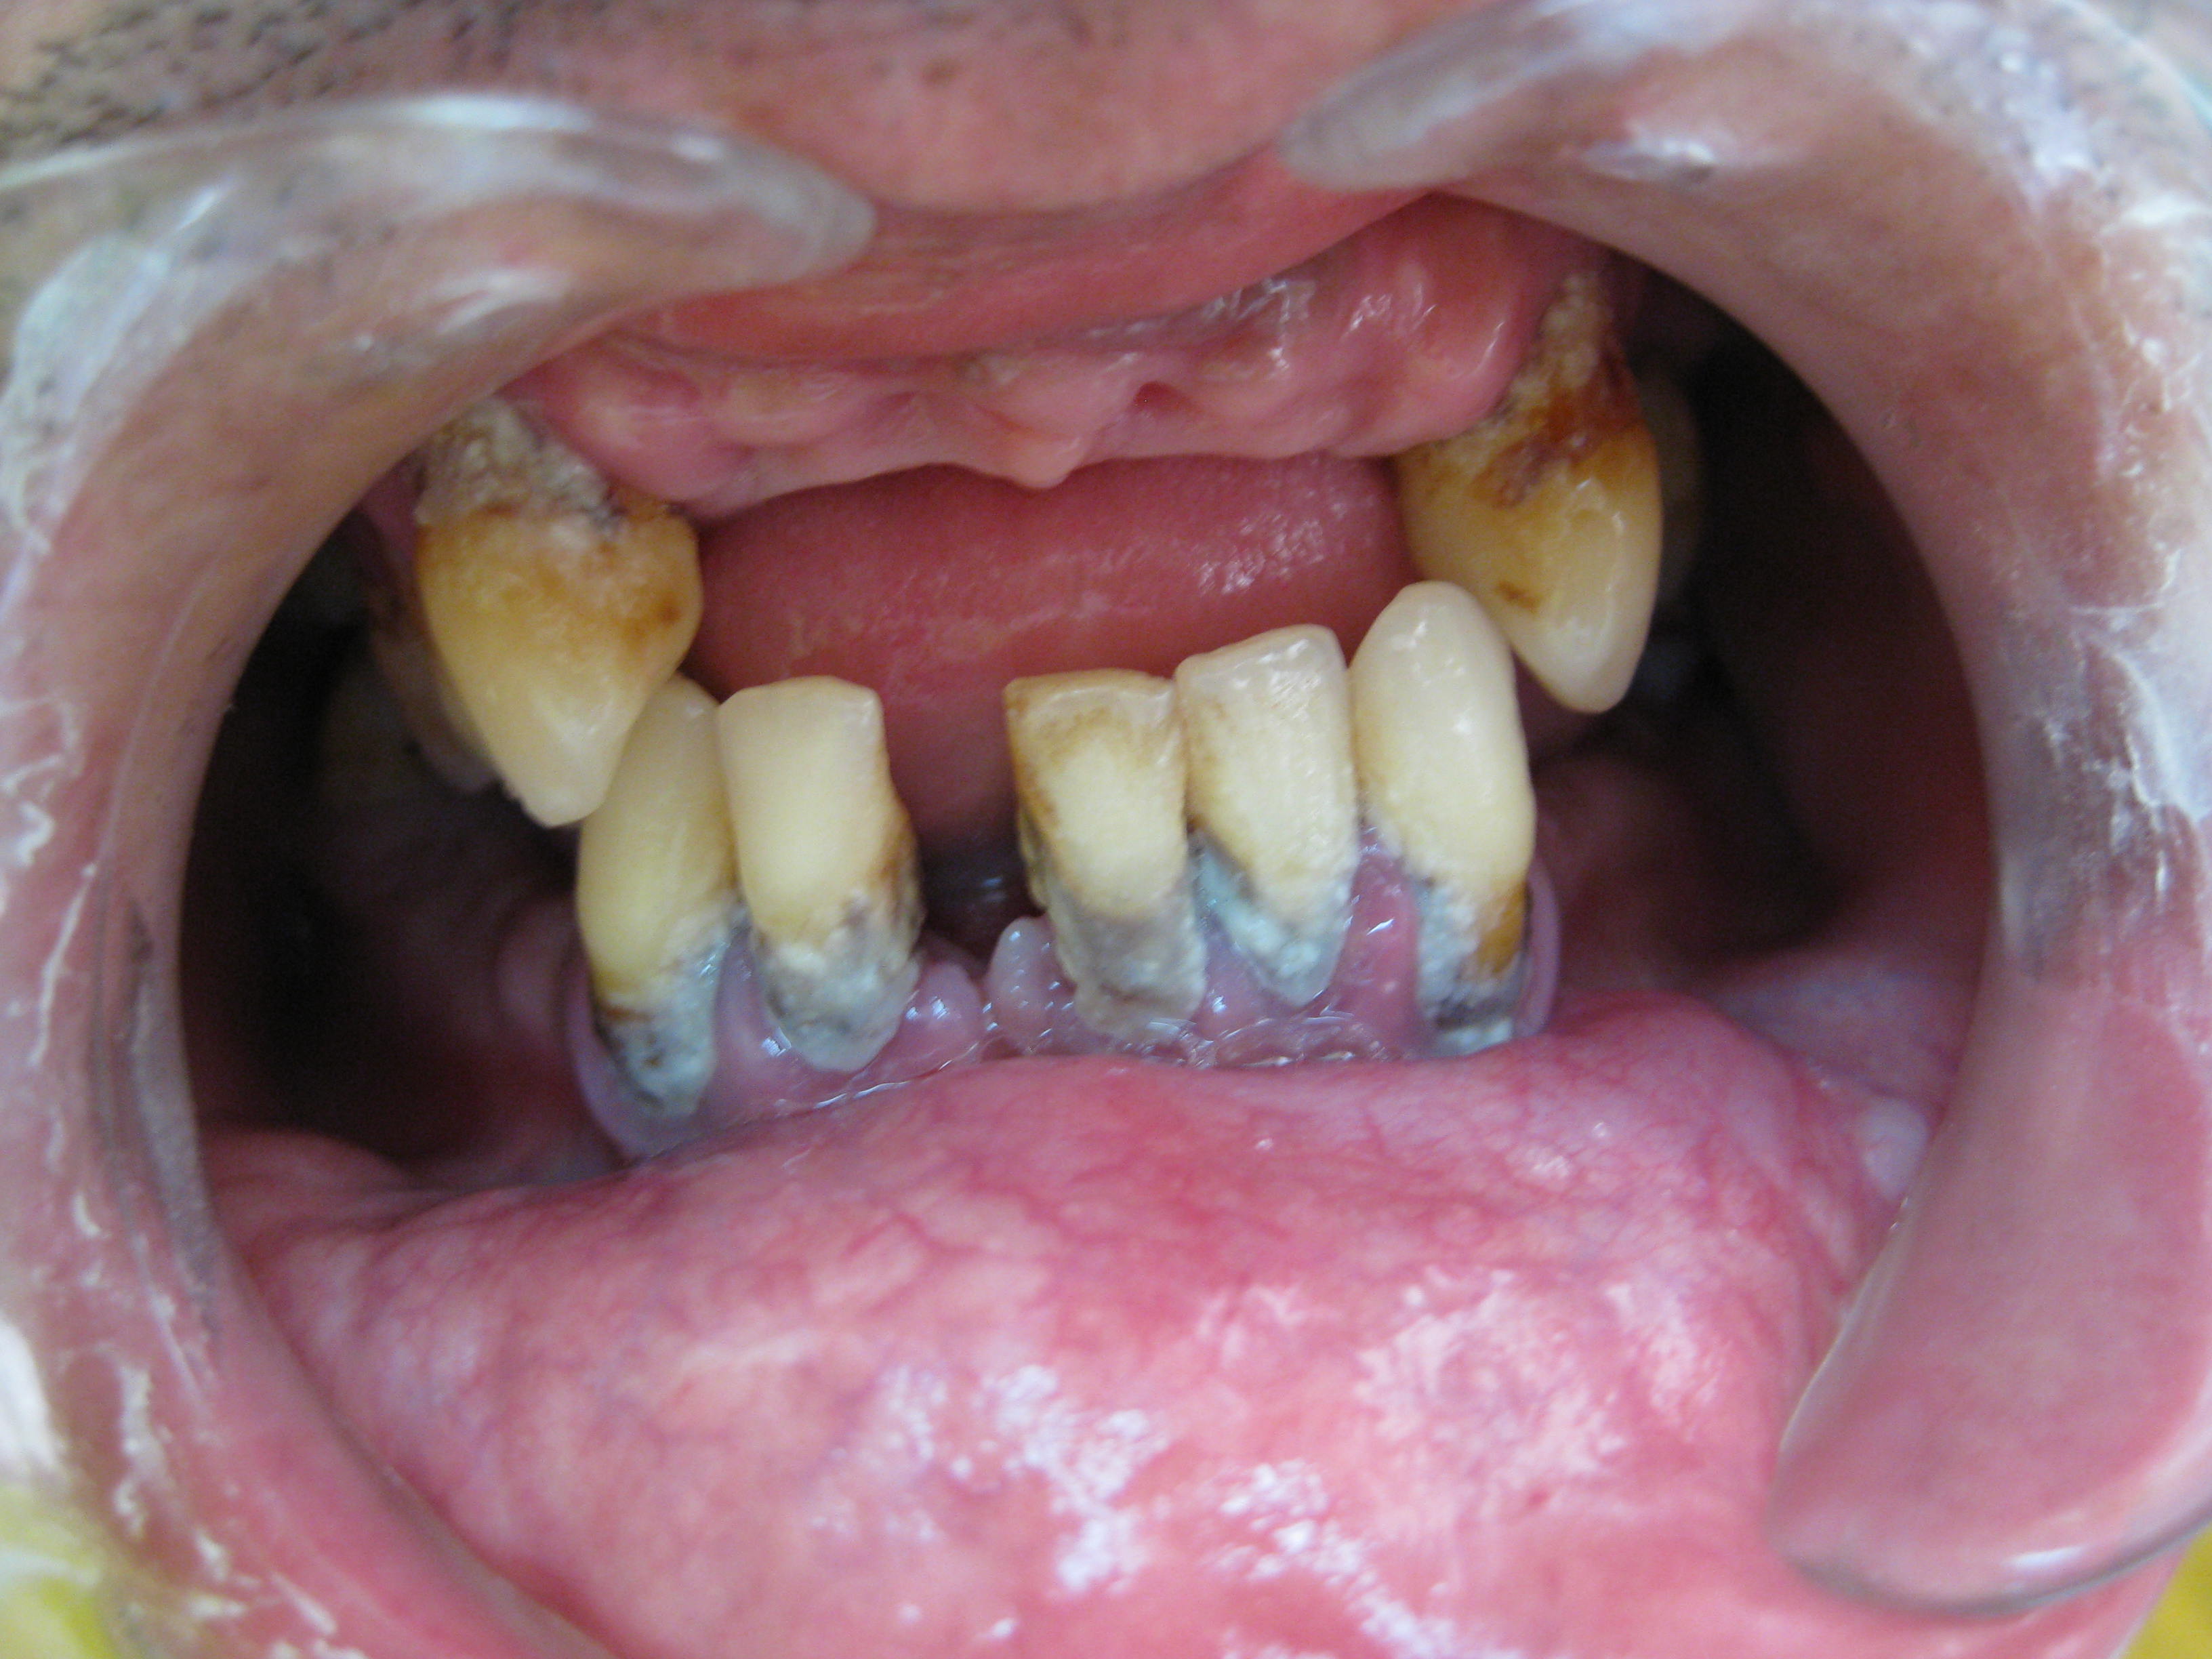

Nas gengivites, é suficiente uma melhoria da higiene oral pelo doente e um tratamento de profilaxia, rápido e fácil. Nas periodontites, o tratamento desenrola-se em várias fases. Em primeiro lugar, realiza-se um estudo periodontal clínico e radiológico para avaliar a situação, fazer um diagnóstico e traçar um plano de acção. Seguidamente, efectua-se a fase básica do tratamento para remoção da placa bacteriana da bolsa periodontal, que se designa como raspagem e alisamento radicular. Em bolsas profundas é necessário fazer, adicionalmente, uma pequena cirurgia periodontal correctiva. Após a doença estar controlada, inicia-se a fase de tratamento de manutenção.